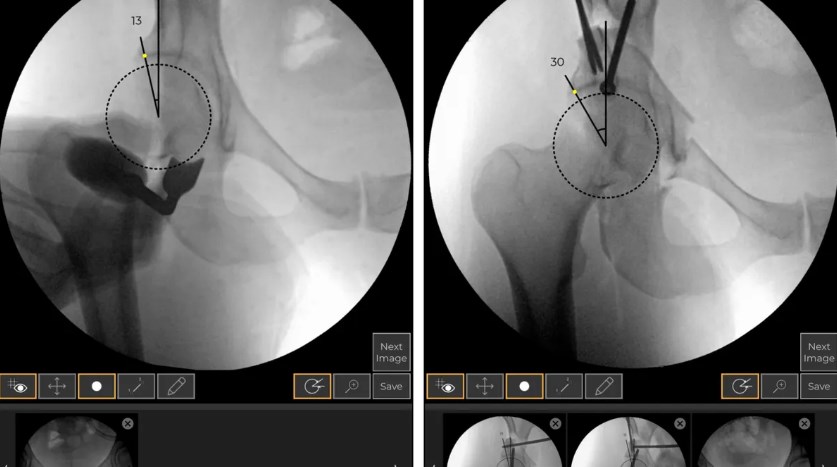

总部位于盐湖城的 Orthogrid 使用透视成像来帮助外科医生在髋关节手术过程中跟踪植入物的位置。它还拥有另外两种美国食品和药物管理局批准的用于髋关节保护和创伤手术的解决方案。

通过使用透视而不是 CT 扫描,Orthogrid 可以为手术室提供实时导航和更高效的工作流程。